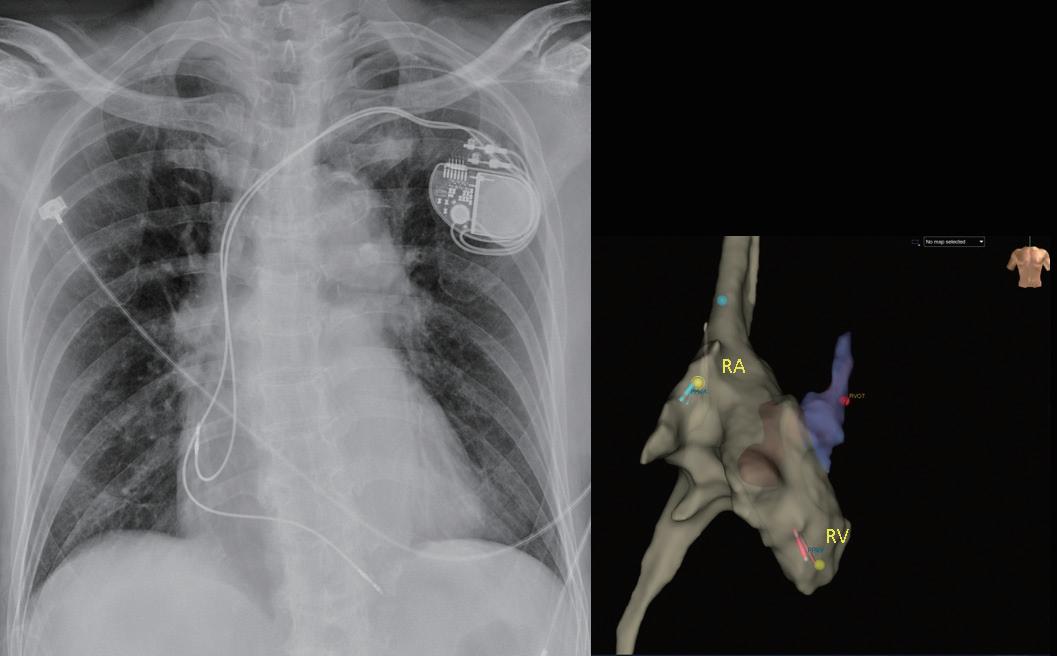

臺大兒童醫院兒童心臟科在吳美環教授與邱舜南 教授的率領下,於 2016 年底開始進行無輻射心律不 整燒灼,並於 2018 年開始發展 EnSite Precision 心臟 定位系統輔助進行無輻射心臟植入性電子儀器放置。 病患在以 propofol 鎮靜和 lidocaine 局部麻醉後,藉由 無菌的超音波即時導引技術,穿刺左鎖骨下靜脈或左 腋靜脈並留置導線(圖一),接著先於鎖骨下區域手

術製造皮下口袋(subcutaneous pocket)後,再以導線 經 Seldinger technique 建立靜脈的通道。接著,藉由 EnSite Precision 心臟定位系統,使用可控式 10 極導管 ( InquiryTM, steerable diagnostic catheter, SJM ), 自左鎖骨下靜脈、頭肱靜脈 , 上、下腔靜脈、右心房 以及右心室等立體結構,進行心血管系統之 3D 繪製 (圖二)。繪製時,會特別著重右心耳、右心尖與右 心室出口的結構與位置,以利後續置放進行。接著, 將心臟植入性電子儀器的導線連結於 EnSite 系統並成 像,在 3D 定位系統導引下,由先前繪製的構造中, 將導線尖端置於目標處(圖三),並進行相關參數測 試。選定適當位置進行導線固定時,由於目前系統無 法將主動固定的螺旋( screw)成像,因此無法確認螺 旋是否確實伸展。我們團隊於此步驟會藉由螢光檢查 檢視螺旋伸展的狀況、評估放置位置是否與預期相符 以及導線鬆弛程度( lead slack)是否適當。調整後, 完成心臟植入性電子儀器放置時,亦會再藉由螢光檢 查確認位置(圖四)。目前臺大單一中心經驗,藉由 3D 定位系統於 13 個病人中放置過 14 個儀器(3 個單 腔節律器、6 個雙腔節律器、4 個植入式心內去顫器及 1 例心臟再同步治療裝置),平均輻射暴露時間約為 0.6 分鐘,相較於傳統方式(平均輻射暴露時間為 10.3 分 鐘)明顯少許多。目前無觀察到相關術後併發症,且 各儀器的追蹤參數與傳統置入的儀器無差別。 相較於置放節律器與植入式心內去顫器,心臟再 同步治療裝置的更為複雜,因為需將導線置於冠狀 靜脈竇(coronary sinus, CS),可能需要藉由顯影劑 讓 CS 顯像,且所需的輻射暴露時間常為前兩者的數 倍 (14),病人與執行醫師的輻射暴露也最強,過去甚至 有研究建議一位醫師單月放置心臟再同步治療裝置數 目勿超過四個,以控制在較安全的輻射曝露量 (15)。

中華民國心律醫學會‧ Taiwan Heart Rhythm Soclety ‧中華民國 111 年 9 月出刊 ( 圖三 ) ( 圖ㄧ ) ( 圖二 ) ( 圖四 ) vs 101.4 秒 , p<0.001),16 位無輻射導引組執行過 程 的輻射暴露時間 < 1 秒,使用於螺旋旋入後之確認影 像,兩組病人於手術當下、一週與 4 到 6 週的追蹤皆 無併發症,並且於追蹤導線電阻(impedance)、相關 閾值(包括 capture voltage, capture time)等皆無差別, 可謂兩組放置成效相仿 (16)。對於使用無輻射導引置放 CIED 的過程,何時要使用螢光檢查確認,依不同醫學 中心的習慣而異。有個案報告於懷孕婦女中,在術中 以心臟內超音波評估導線鬆弛程度(lead slack);或 以更換不同曲度的探針( stylet)而導線尖端位置維持 不變,做為螺旋順利旋入的間接證據,來達成完全零 輻射暴露的 CIED 置放。然而大部分的中心,仍常規 於螺旋固定後,以螢光檢查影像進行相關確認 (10,11,16)。 當面臨血管解剖構造有變異、導管產生糾結或是冠狀 靜脈竇無法完整繪製的狀況,螢光檢查仍佔重要的輔 助角色 (11)。 3D 定位系統於介入性心臟電生理學的領域,未來將 佔據更重要的角色,對於構造複雜的先天性心臟病患者, 因其血管走向常不典型,過往治療可能造成多處心肌纖 維化或高度累積輻射暴露,以無輻射導引方式進行介入 性心臟電生理治療與儀器置放,有其優勢與必要性 (17)。 現階段因為各國技術上仍未標準化,此技術尚未普及, 也缺乏大型研究分析其成效與安全性,針對長期預後以 及是否符合成本效益,還有賴未來研究證實。不過在執 行數量增加後,執行時間預期可以降低且可大幅度降低 輻射暴露,相信在不久的未來,能為病患與醫療團隊, 建構更安全、有效率的醫療環境。